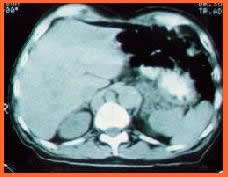

Tomografía Computarizada abdominal

Durante su tratamiento oncológico, una Tomografía abdominal de control, demostró la presencia de lesiones nodulares, en ganglios para aórticos semejantes a los descritos en el tórax de aspecto metastásico. Que presentaron involución durante el tratamiento descrito.